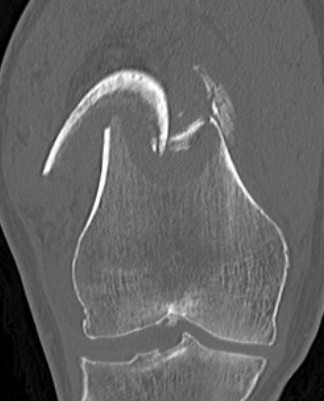

Supracondylar Femur

Options

Plate / dual plate

Retrograde nail

Modular knee prosthesis